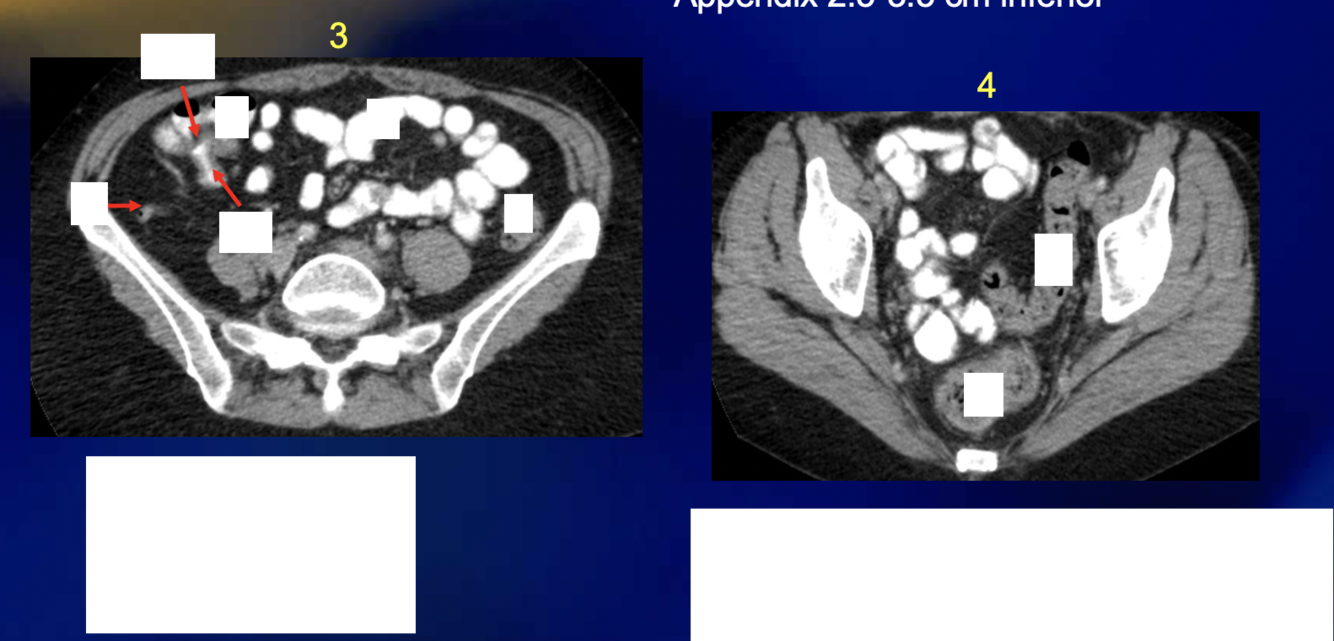

If a person has appendicitis and their appendix is retrocecal, they will likely present with […] pain

If a person has appendicitis and their appendix is pelvic, they will likely present with […] pain

Shoulder

RLQ

The appendix is [….]peritoneal

Intra